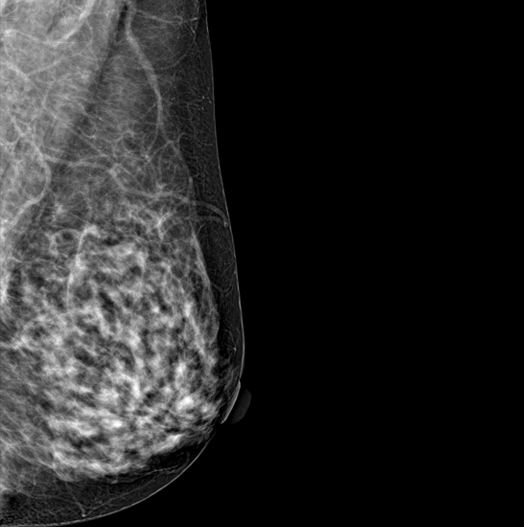

SYNTHESIZED 2D

HESTIA supports "Synthetic 2D" that generates 2D images only by tomography shooting without additional 2D shooting.